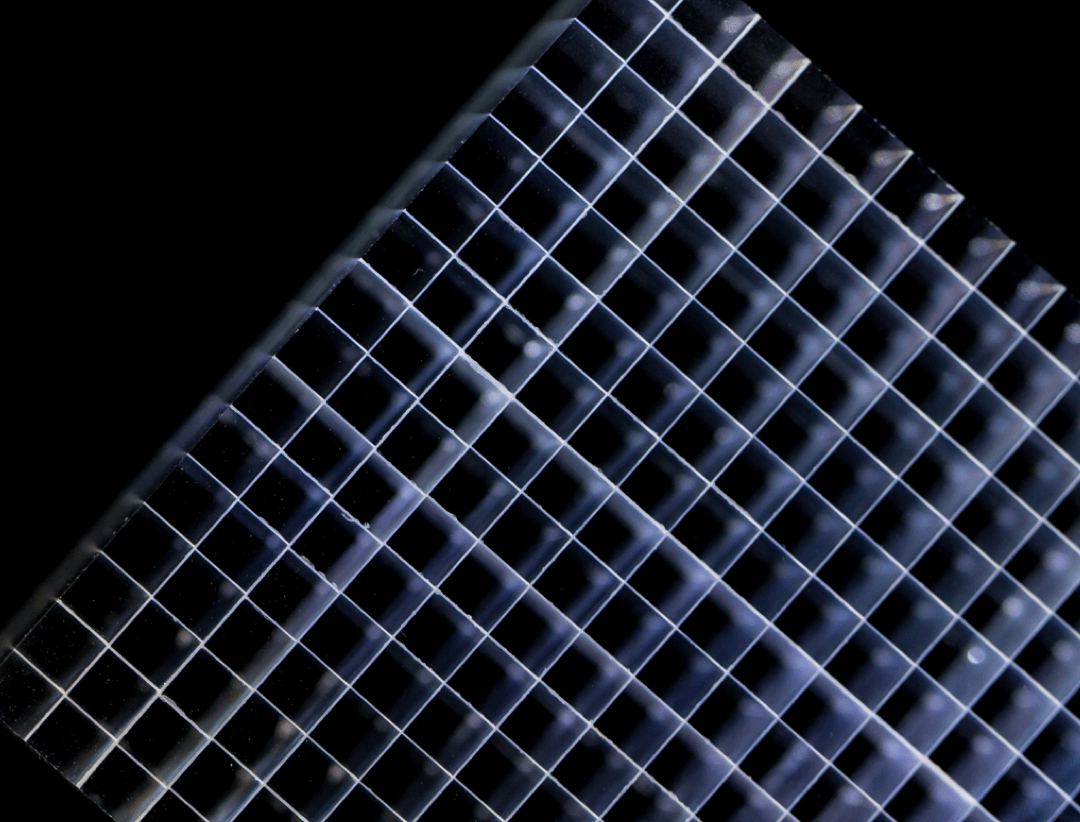

600 x 600

超大矩阵,高精度超清重建